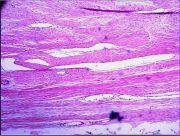

| 2021年12月10日 (五) 13:16 | 14号切片-纤维肉瘤-镜下观6.jpg (文件) |  |

135 KB | Cirno.9 | 基于MsUpload的文件上传 | 1 |

| 2021年12月10日 (五) 13:16 | 14号切片-纤维肉瘤-镜下观5.jpg (文件) |  |

139 KB | Cirno.9 | 基于MsUpload的文件上传 | 1 |

| 2021年12月10日 (五) 13:16 | 14号切片-纤维肉瘤-镜下观4.jpg (文件) |  |

125 KB | Cirno.9 | 基于MsUpload的文件上传 | 1 |

| 2021年12月10日 (五) 13:15 | 14号切片-纤维肉瘤-镜下观3.jpg (文件) |  |

193 KB | Cirno.9 | 基于MsUpload的文件上传 | 1 |

| 2021年12月10日 (五) 13:15 | 14号切片-纤维肉瘤-镜下观2.jpg (文件) |  |

143 KB | Cirno.9 | 基于MsUpload的文件上传 | 1 |

| 2021年12月10日 (五) 13:15 | 14号切片-纤维肉瘤-镜下观1.png (文件) |  |

519 KB | Cirno.9 | 基于MsUpload的文件上传 | 1 |